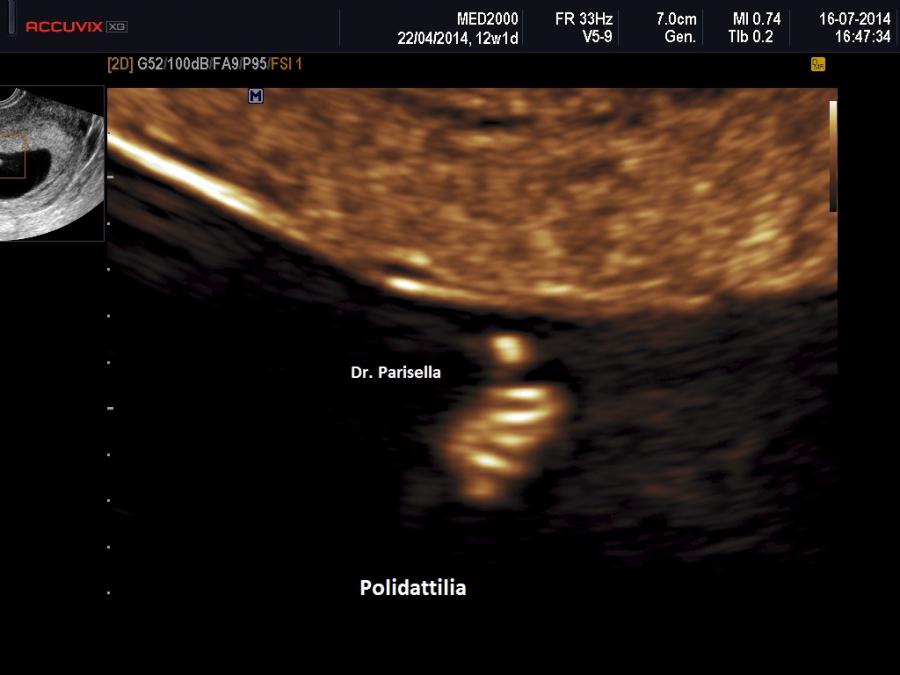

All'esame ecografico prenatale le caratteristiche che indirizzano verso la diagnosi sono:

3) la polidattilia è di tipo postassiale ed è pressocchè costante alle mani